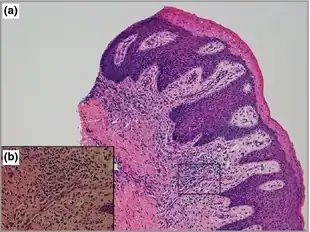

Congenital hemidysplasia with ichthyosiform erythroderma and limb defects (also known as "CHILD syndrome") is a genetic disorder with onset at birth seen almost exclusively in females.[1]: 485 The disorder is related to CPDX2, and also has skin and skeletal abnormalities, distinguished by a sharp midline demarcation of the ichthyosis with minimal linear or segmental contralateral involvement.[1]: 501

- I - Ichthyosiform Erythroderma—At birth or shortly after birth, there are red, inflamed patches (erythroderma), and flaky scales (ichthyosis) on the side of the body that is affected. Hair loss on the same side may also be possible.

The symptoms would appear at birth or shortly after birth. The combination of physical symptoms on the child would suggest they have CHILD syndrome. A skin sample examined under a microscope would suggest the characteristics of the syndrome and an X-ray of the trunk, arms, and legs would help to detect underdeveloped bones. A CT scan would help detect problems of the internal organs.